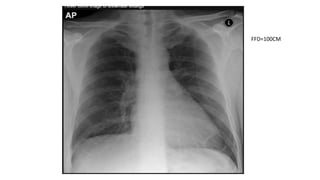

Anterioposterior view

• AP-supine

• Used when patient is debilitated

,immobilized or unable to tolerate

standing

• With assistance, a cassette is carefully

positioned under the patient’s chest

with the upper edge of the cassette

above the lung apices.

• The arms are rotated laterally and

supported by the side of the trunk. The

head is supported on a pillow, with the

chin slightly raised.

• Patient is asked to take a deep breath

(if possible) and xray is taken

FFD=100CM

Anterioposterior view • AP-supine •Used when patient is debilitated ,immobilized or unable to tolerate standing • With assistance, a cassette is carefully positioned under the patient’s chest with the upper edge of the cassette above the lung apices. • The arms are rotated laterally and supported by the side of the trunk. The head is supported on a pillow, with the chin slightly raised. • Patient is asked to take a deep breath (if possible) and xray is taken FFD=100CM